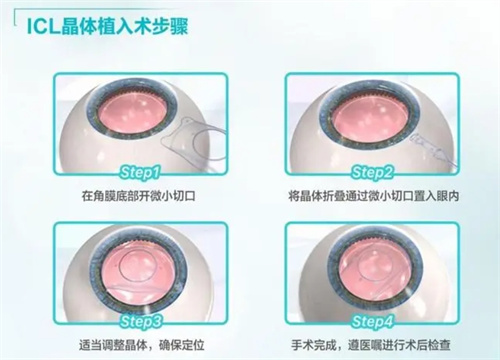

人工晶体植入术(ICL)通过在眼内植入一个特殊的人工晶体来矫正视力,这种手术避免了切削角膜的风险,且对角膜厚度没有严格要求。对于近视度数高达1500度的患者来说,这种手术方式可能更为适合。ICL手术适应的近视度数范围广泛,通常可矫正300度到2300度的近视,以及600度以下的散光。